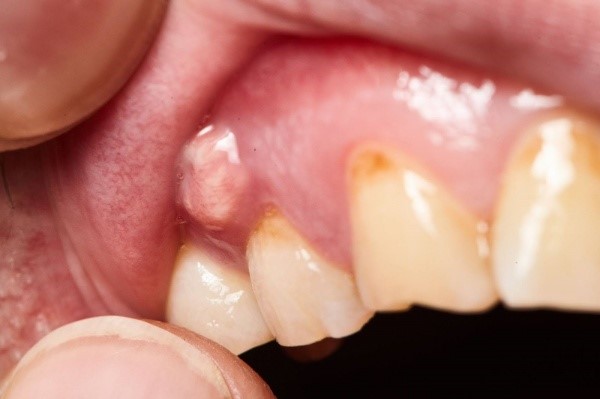

- Có tình trạng sưng nướu, có thể xuất hiện mủ hay sưng cả vùng má. Bạn có thể nhận thấy nướu răng sưng đỏ và đau khi chạm vào. Áp xe răng thì có thể bị khối phồng mềm chứa mủ viêm.

Viêm quanh cuống